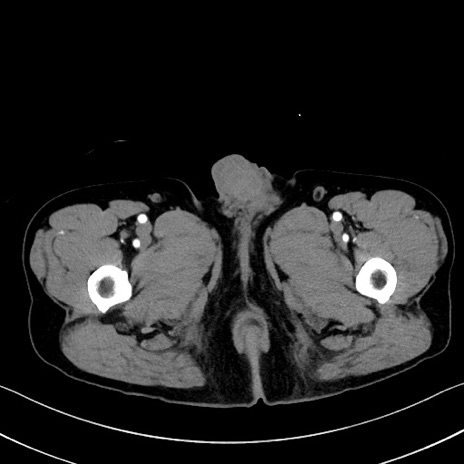

症例35(横断像)

【症例】70歳代 男性

【主訴】腹部膨満、嘔吐

【現病歴】昨日より腹部膨満感出現。本日増悪し、仙痛出現。嘔吐あり、受診。

【既往歴】糖尿病、胆摘後

【身体所見】BP 149/80mmHg、HR 74/min、BT 35.9℃、腹部:膨満、軟、圧痛なし。腸雑音減弱あり。上腹部正中切開瘢痕あり。

【データ】WBC 13500、CRP 1.72